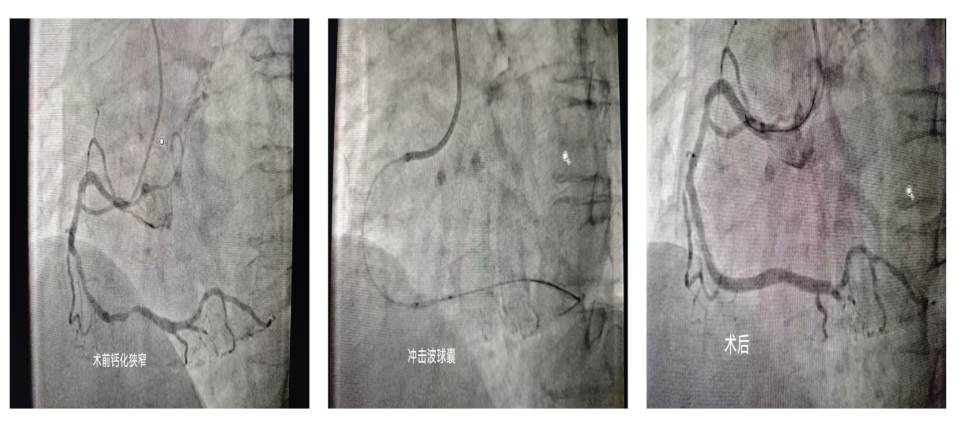

術(shù)前術(shù)后對比

專業(yè)特長:擅長心內(nèi)科各類疾病、疑難復雜心血管疾病的診斷及治療。擅長復雜冠狀動脈介入治療、先心病介入封堵術(shù)、心臟起搏器植入等新技術(shù),開展左主干病變、分叉病變、鈣化病變、慢性閉塞病變等介入治療,開展冠脈血管內(nèi)超聲(IVUS)腔內(nèi)影像學診斷,鈣化病變冠脈內(nèi)旋磨治療,逆向?qū)Ыz技術(shù)開通CTO病變,開展主動脈球囊反搏(IABP)聯(lián)合體外膜肺氧合(ECMO)支持下重癥患者的冠脈介入治療,達到省內(nèi)先進水平。